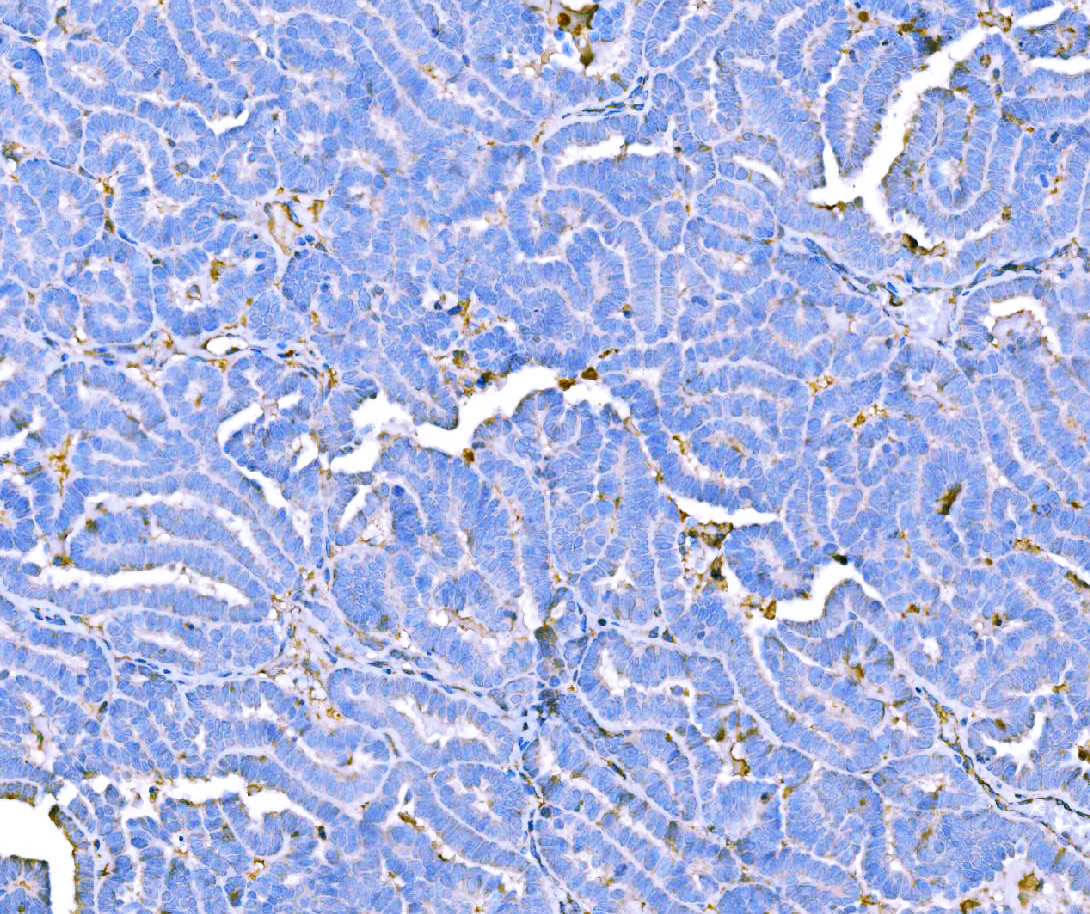

IHC analysis of F2 using anti-F2 antibody (M00044-2).

F2 was detected in a paraffin-embedded section of human Ovarian cancer tissue. Biotinylated goat anti-mouse IgG was used as secondary antibody. The tissue section was incubated with mouse anti-F2 Antibody (M00044-2) at a dilution of 1:200 and developed using Strepavidin-Biotin-Complex (SABC) (Catalog # SA1021) with DAB (Catalog # AR1027) as the chromogen.